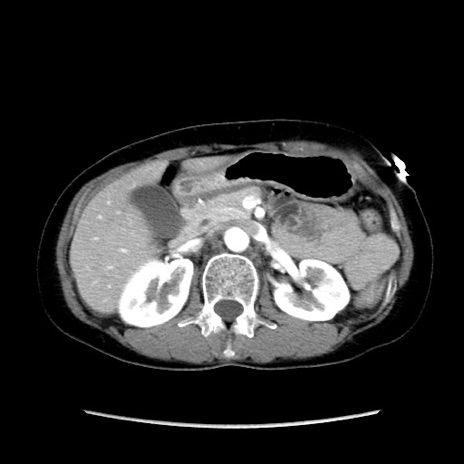

症例32(横断像)

【症例】40歳代 女性

【主訴】上腹部痛、嘔気・嘔吐

【現病歴】約9時間前頃から急に上腹部痛、嘔気、嘔吐が出現。改善しないため救急要請。

【既往歴】子宮頚癌(広汎子宮全摘術、放射線療法)、腸閉塞

【身体所見】腹部:平坦、軟、腸雑音亢進、上腹部を中心に腹部全体に圧痛あり。

【データ】WBC 8400、CRP 0.03